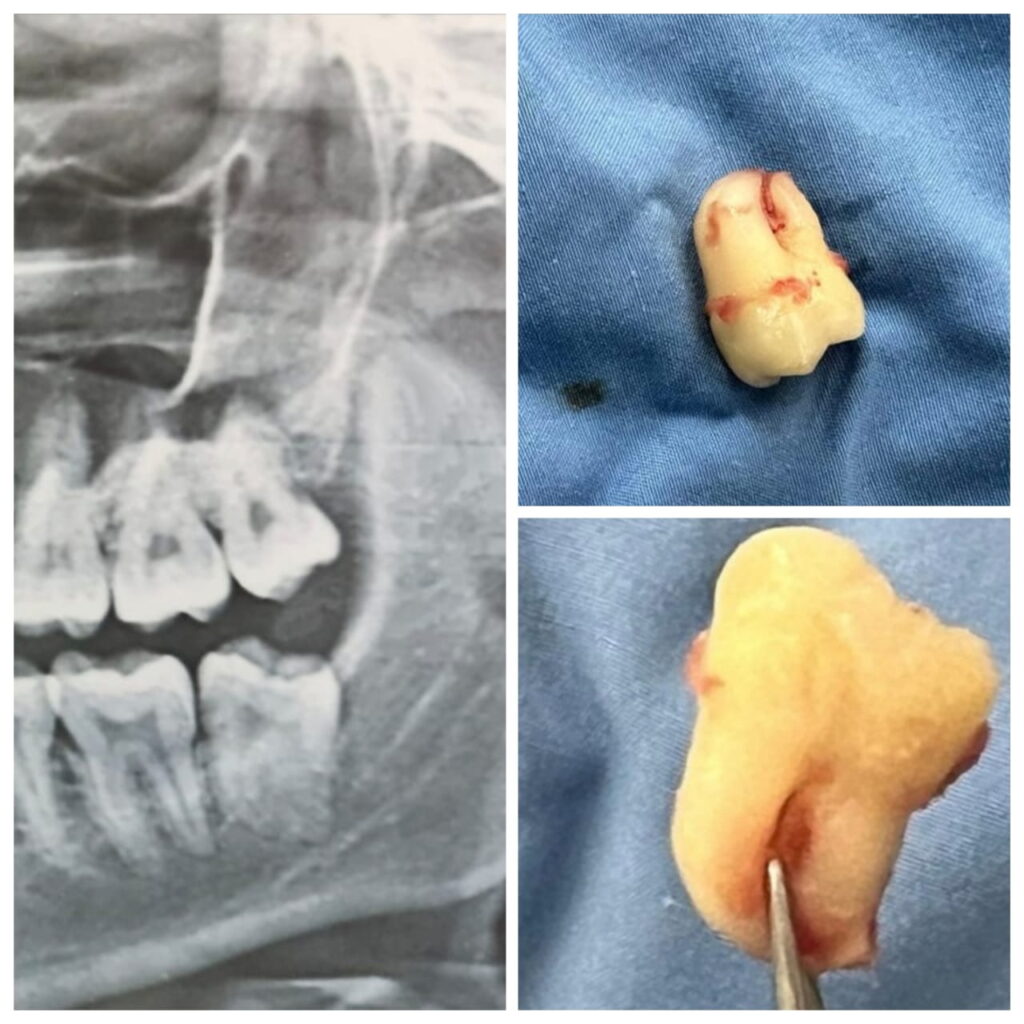

Surgical Removal Of Impacted Teeth